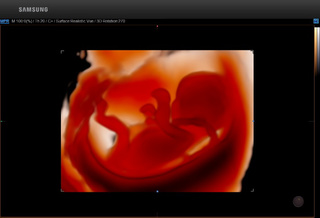

5D超声能够全方位、多角度评估胎儿生长发育情况,广泛应用于胎儿染色体异常所致畸形(NT测量)、胎儿长骨畸形、胎儿心脏畸形、胎儿中枢神经系统畸形等产前筛查的各个领域。

5D智能超声通过大样本的数据分析,智能识别胎儿产前筛查所需多种标准切面,自动进行多项数据测量。对胎儿畸形的早期诊断提供比传统四维彩超更精确的数据!